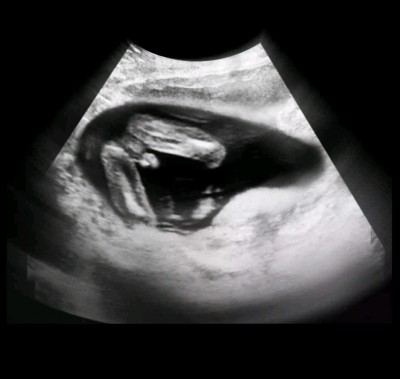

Kızlar 24 haftadayım ama bir türlü bebeğimin cinsiyetini tam bilen çıkmadı biri diyor kız biri erkek hayırlısı olsun Rabbim sağlıkla hepimizin bebeğini kucağına aldırmayı nasip etsin ama insan merak ediyor bu ikinci gebeliğim ilk kızımda böyle şey başıma gelmedi birde siz bakarmisiniz

Gebelik haftası 24+1

Valla erkeğe de benzettim ama kız da olabilir Kordonsa eğer o çıkıntı bilemedim :) doktorlar daha iyi bilir farklı pozisyonlardan da bakıyorlar

Bence kiz.dikkatli bakarsaniz 3 adet cizgi var sanki elini koymus bacak arasina

Bebeğiniz erkek bu sayfada da arasında kurbağa şekli gibiyse erkek hamburger gibi yuvarlaksa kız yazıyor burda yuvarlaklik yok yada ben öyle görüyorum hayırlısı inşallah